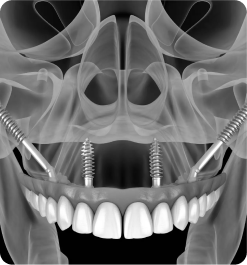

CREDENCIAMENTO EM FIXAÇÕES ZIGOMÁTICAS E APERFEIÇOAMENTO NAS TÉCNICAS ALL ON FOUR

Coordenação: Paulo Abdalla Saad

• Prática clínica em pacientes!

IMERSÃO EM CIRURGIA GUIADA

Coordenação: Paulo Abdalla Saad

• Teórico

• Prático

• Demostrativo

IMERSÃO NA TÉCNICA ALL-ON-FOUR

Coordenação: Dr. Marcelo Zamperlini

Público alvo: Cirurgiões dentistas Implantodontistas, Periodontistas e Bucomaxilofaciais.

Curso prático de 3 dias | Material Incluso para todas as Práticas.

IMERSÃO ZIGOMA DAY

Coordenação: Dr. Marcelo Zamperlini

Público alvo: Cirurgiões dentistas Implantodontistas, Periodontistas e Bucomaxilofaciais.

Curso prático de 3 dias | Material Incluso para todas as Práticas.

• Prótese Protocolo

• Implantodontia

• Implantes Zigomáticos